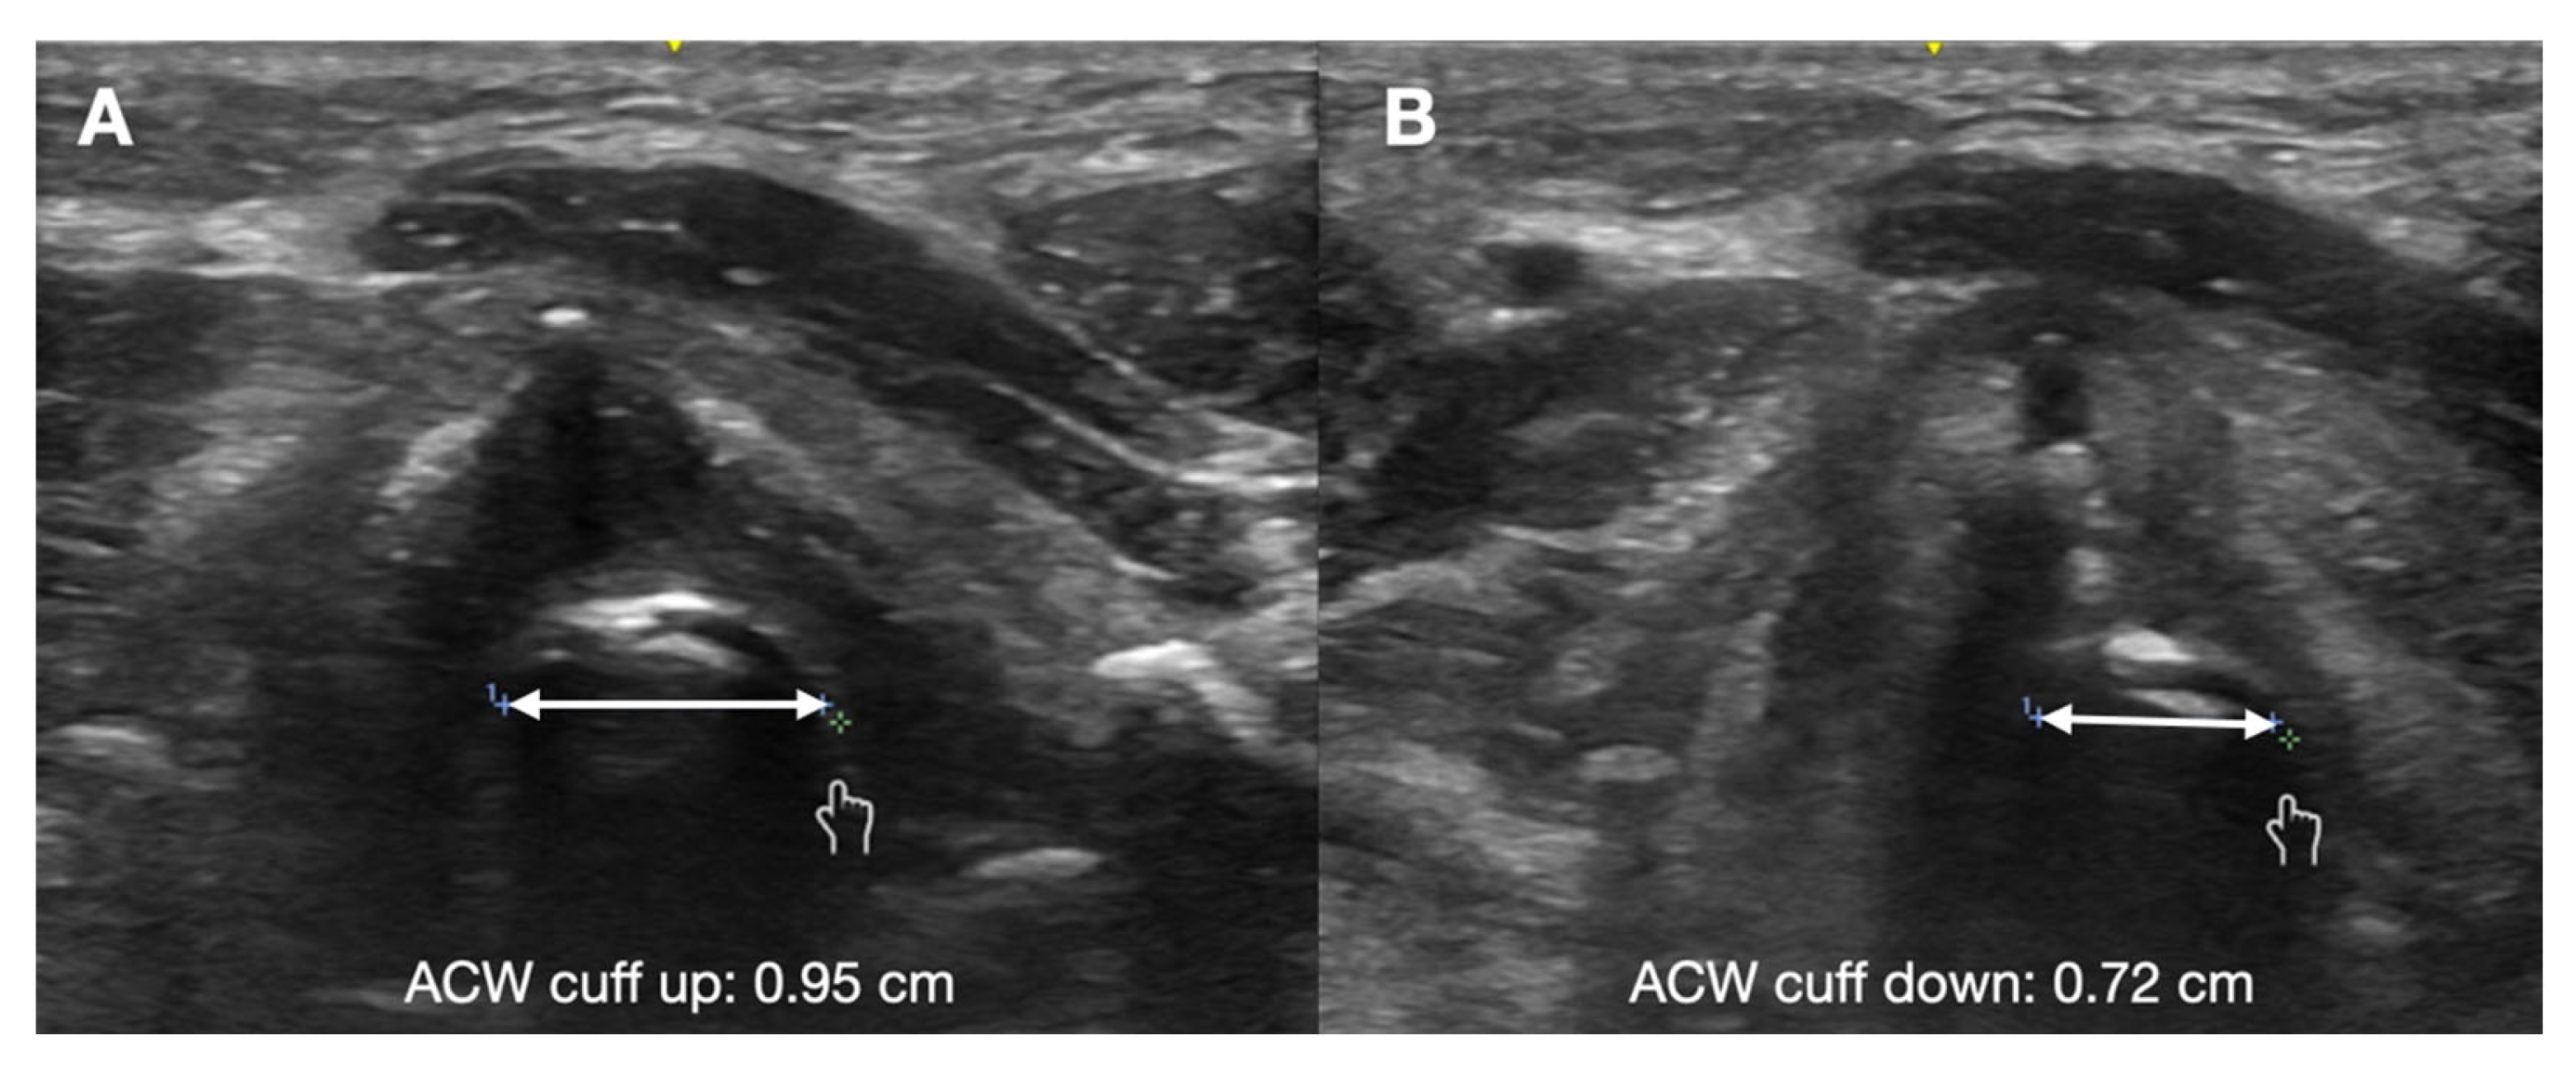

7. Assessment of Laryngeal Edema

- Mikaeili, H.; Yazdchi, M.; Tarzamni, M.K.; Ansarin, K.; Ghasemzadeh, M. Laryngeal ultrasonography versus cuff leak test in predicting postextubation stridor. J. Cardiovasc. Thorac. Res. 2014, 6, 25–28. [Google Scholar]

- El Amrousy, D.; Elkashlan, M.; Elshmaa, N.; Ragab, A. Ultrasound-Guided Laryngeal Air Column Width Difference as a New Predictor for Postextubation Stridor in Children. Crit. Care Med. 2018, 46, e496–e501. [Google Scholar] [CrossRef]

- Ding, L.W. Laryngeal ultrasound: A useful method in predicting post-extubation stridor. A pilot study. Eur. Respir. J. 2006, 27, 384–389. [Google Scholar] [CrossRef] [PubMed]

- El-Baradey, G.F.; El-Shmaa, N.S.; Elsharawy, F. Ultrasound-guided laryngeal air column width difference and the cuff leak volume in predicting the effectiveness of steroid therapy on postextubation stridor in adult. Are they useful? J. Crit. Care 2016, 36, 272–276. [Google Scholar] [CrossRef]

- Tsai, W.W.; Hung, K.C.; Huang, Y.T.; Yu, C.H.; Lin, C.H.; Chen, I.W.; Sun, C.K. Diagnostic efficacy of sonographic measurement of laryngeal air column width difference for predicting the risk of post-extubation stridor: A meta-analysis of observational studies. Front. Med. 2023, 10, 1109681. [Google Scholar] [CrossRef] [PubMed]